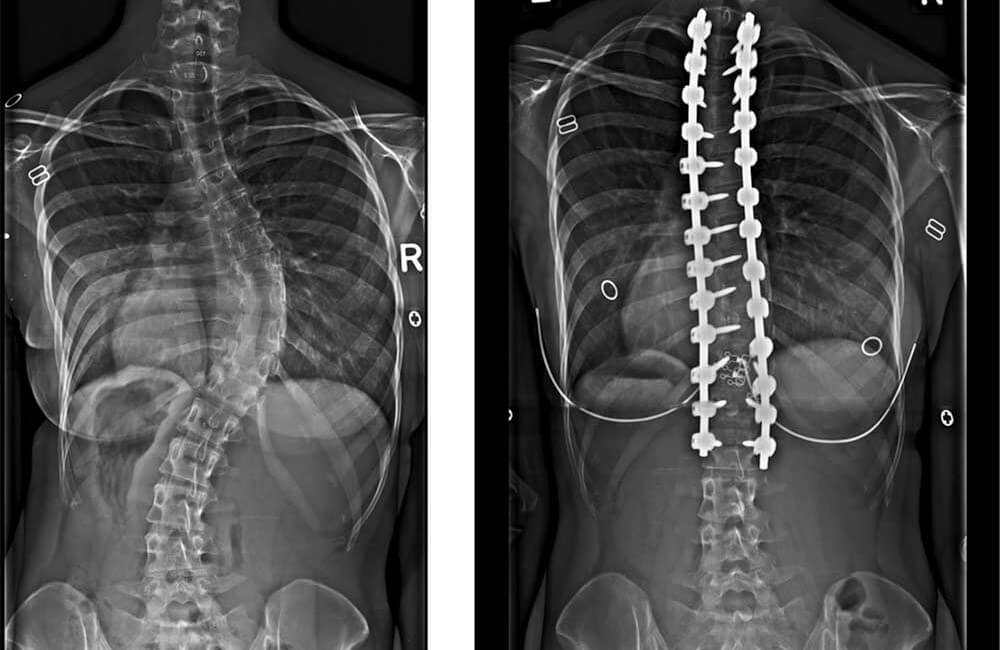

Operatie pe coloana vertebrala. Cu toate acestea cele mai frecvente cauze ale durerii persistente sunt leziunile nervilor de la hernia de disc in sine. Orice operatie pe coloana vertebrala vine cu riscul de a deteriora nervii sau maduva spinarii. A facut operatie si i au pus tija si 2 suruburi un surub i a fost scos pe 8 iunie.

Buna seara numele meu este ani am 49 de ani sant din constanta si sant operata pe coloana in urma cu 3 luni diacnosticul fiind instabilitate vertebrala l1 l2 abord posterolateral cu artrectomiel1 l2de partea dreapta discectomial1 sinteza intersomaticacu fragmentede os spongilos si cageintervertebrale sintezatraspendicularat12 l3bilateral sinteza osoasa. Forum medical bisturiu cu diagnosticul m51 9g respectiv g57 3rg dureri lombare pe coloana piciorul drept amorțit nu puteam sa ma ridic pe călcâi. Fracturile de coloană se operează cu succes în cadrul secţiei de neurochirurgie a spitalului judeţean din timişoara reprezentând aproape o rutină pentru specialişti. Dureri pe coloana dupa o operatie de disc lombara.